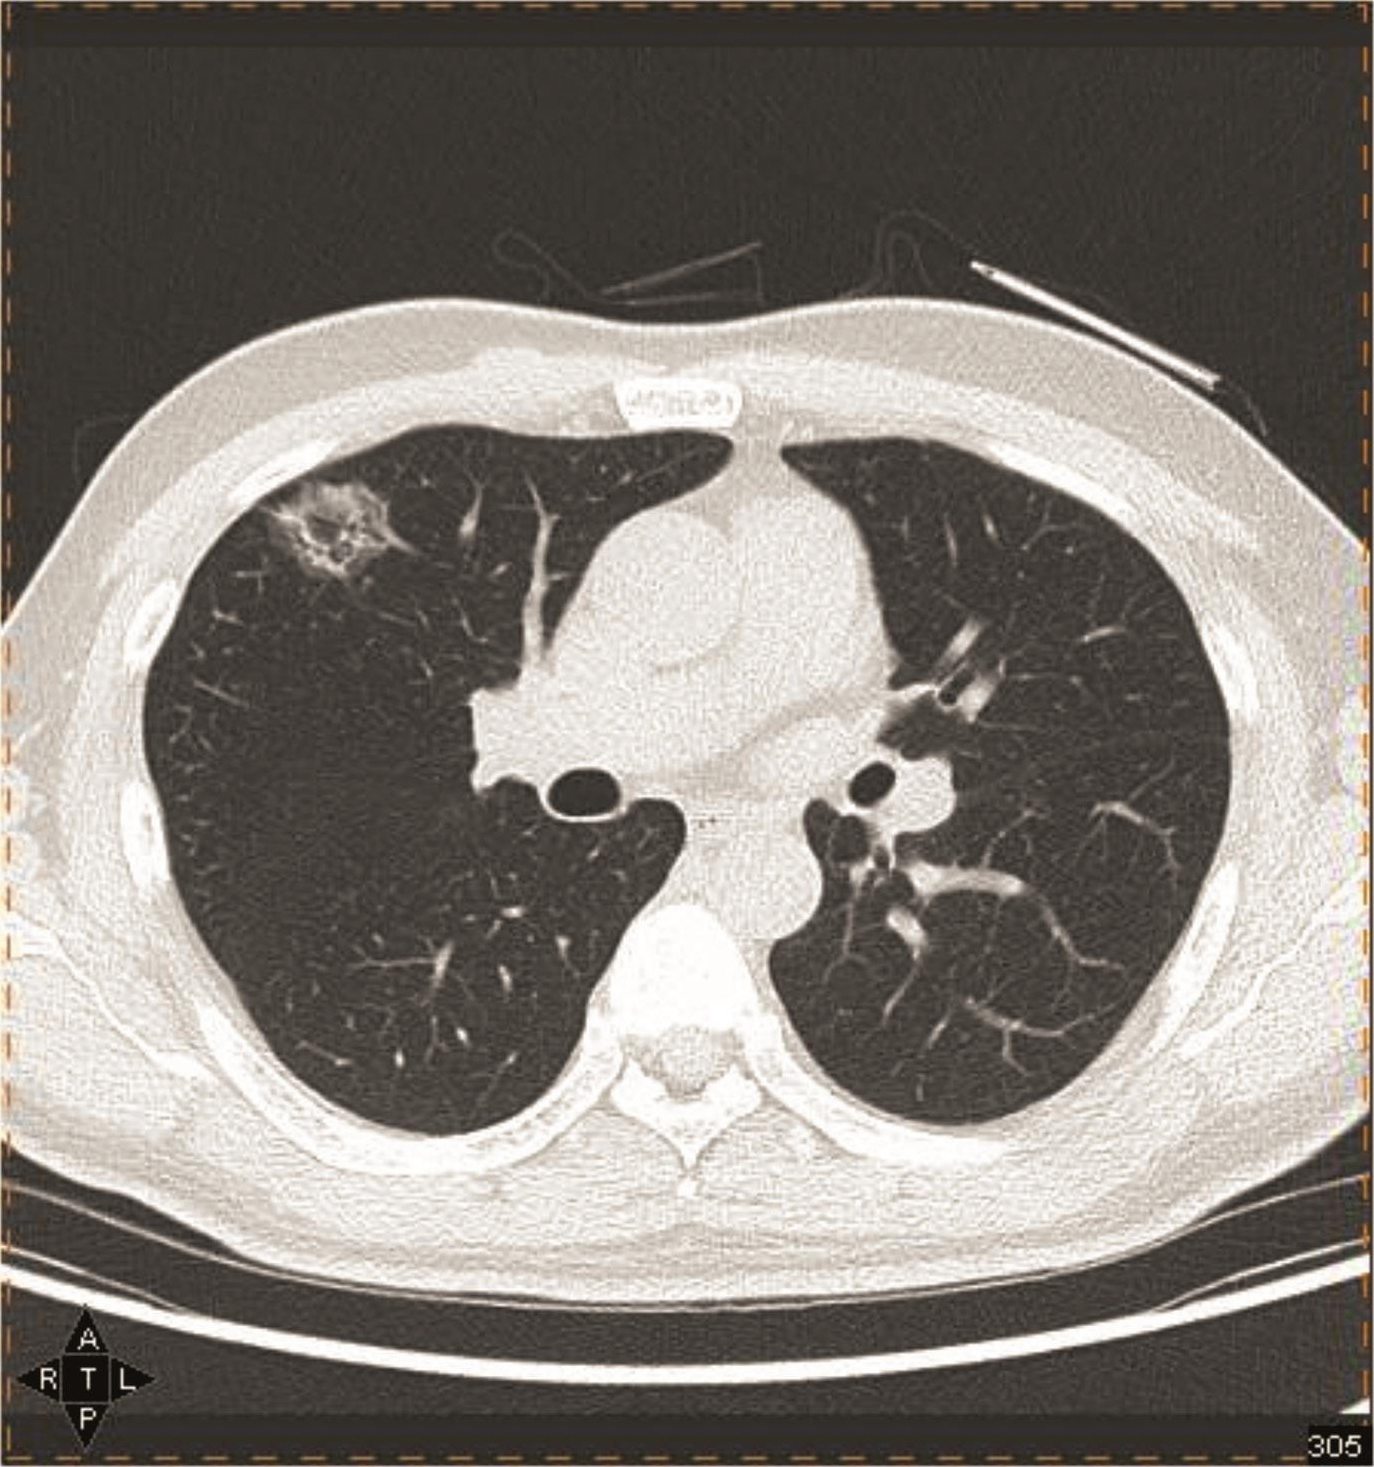

关于petct检查早期肺癌

图片尺寸2200x1650![高尚病例:[pet/ct 肿瘤评效] :Ⅳa 期肺癌治疗 3 月: 可行手术.](https://imgs.wantubizhi.com/img/A1A61BAA66193547F3A6DD7D8EE527E95E72BC4AE56EC14EBB54BE384A31540F65C30CD2A7E857599B7FAC9ED5F34AAFEDD7C113276C07870646CF1DBD18DFB7A72AAD97AAEF2C029937034096E6A645F8BFB1B61C63DA23216F96E91AD4BFF0)

高尚病例:[pet/ct 肿瘤评效] :Ⅳa 期肺癌治疗 3 月: 可行手术.